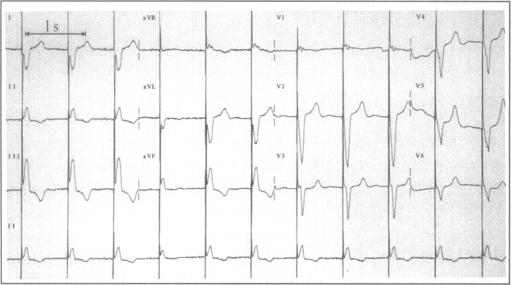

在一名有人工三尖瓣假体的患者中经静脉植入心室起搏导线。

Transvenous implantation of a ventricular pacing lead in a patient with an artificial tricuspid valve prosthesis.

The preference for treatment of symptomatic bradycardia is transvenous right ventricular pacing combined with atrial synchronisation if applicable. In the case of congenital anomalies where no conduit is present between the peripheral veins and the right ventricle, it is not possible to place the ventricular pacing lead in the right ventricle. Also the presence of an artificial valve in the tricuspid position excludes placement of an endocardial right ventricular pacing lead. Since the introduction of biventricular pacing, new guiding catheters and leads used as a transvenous route for left ventricular pacing are available. We report implantation of a ventricular pacing lead in the great cardiac vein for permanent ventricular pacing in a patient with a tricuspid valve prosthesis.

对于有症状的心动过缓,首选治疗方法是经静脉右心室起搏,如适用可联合心房同步起搏。对于外周静脉与右心室之间不存在导管的先天性异常情况,无法将心室起搏导线置于右心室内。此外,三尖瓣位置存在人工瓣膜也排除了心内膜右心室起搏导线的置入。自从双心室起搏引入以来,有了新的引导导管和用作左心室起搏经静脉途径的导线。我们报告了在一名有三尖瓣人工瓣膜的患者中,将心室起搏导线植入心大静脉以进行永久性心室起搏的情况。